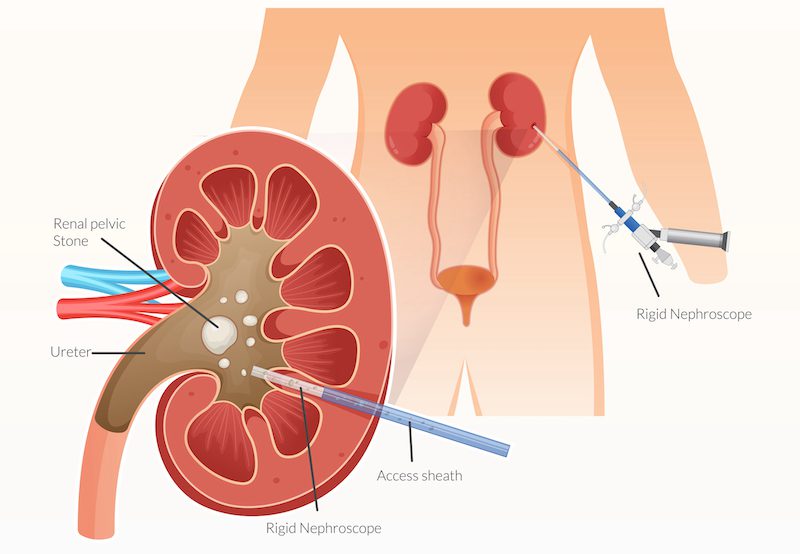

PCNL is performed under general anesthesia. The surgeon makes a small incision in the back to access the kidney directly. A tract is created through which a nephroscope is inserted to locate the stone. Specialized instruments are used to break the stone into smaller fragments, which are then removed.

Ultrasound, X-ray, or CT imaging is often used to guide the procedure for precision. In many cases, a temporary nephrostomy tube is placed to drain urine and ensure kidney function while healing occurs.